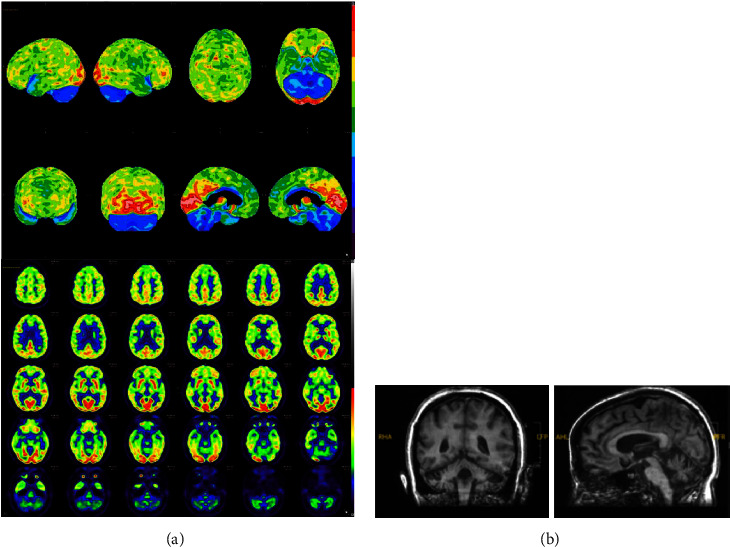

Background: The differential diagnosis of a patient with cognitive, behavioral, and motor symptoms is broad. There is much overlap between neurocognitive disorders due to frontotemporal dementia and other subcortical dementia. A less known diagnosis, cerebellar cognitive affective syndrome (CCAS), should also be considered. Case History. A 29-year-old female presented with ataxia and left-sided weakness. CSF showed oligoclonal bands, and MRI showed multiple white matter lesions with some atrophy. She was diagnosed with multiple sclerosis (MS). At age 35, she developed frontal lobe symptoms and executive dysfunction; she was diagnosed with MS with bipolar disorder. Neuropsychological evaluation at that time showed significant deficits in multiple cognitive domains. Subsequent MRI showed progressive frontotemporal atrophy, and FDG-PET uncovered hypometabolism in the frontotemporal lobes and cerebellum. At age 38, her behavior worsened with aggression, and she was started on olanzapine. She responded well with decreased agitation and improved motivation and attention. Compared with previous scans, most recent MRI and FDG-PET showed interval increase in cerebellar atrophy with increase in hypometabolism in the cerebellum, respectively.

Conclusion: Based on cerebellar, affective, and subcortical cognitive examination findings, our diagnosis is probable CCAS. The cerebellum should be considered as a possible etiology of frontal subcortical cognitive impairment.